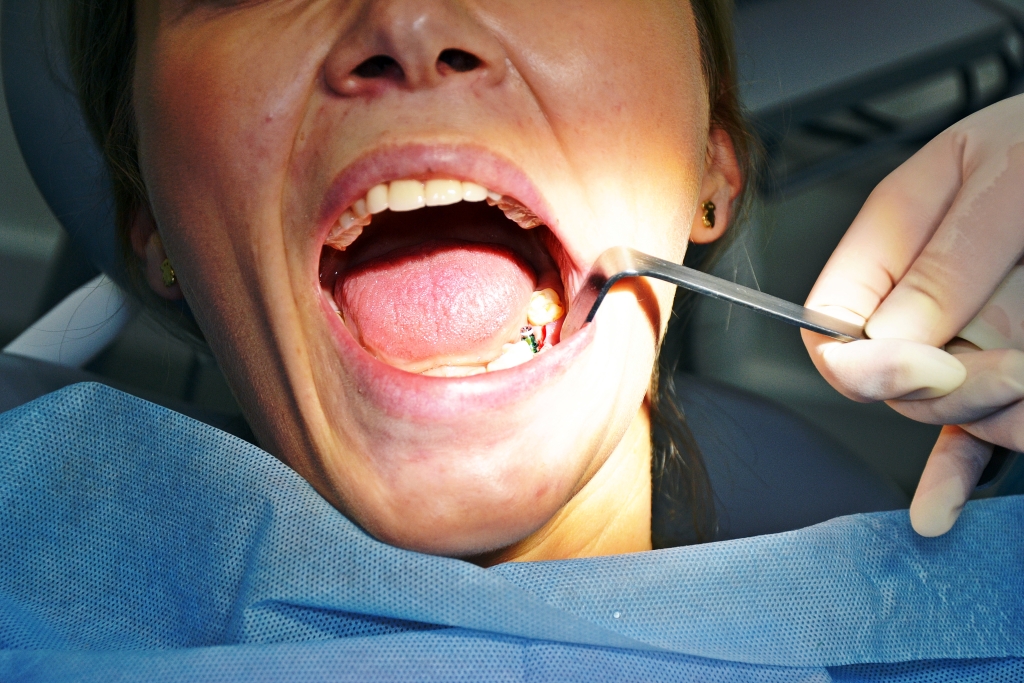

Sam zabieg trwa kilkadziesiąt minut i jest całkowicie bezbolesny. Pacjenta podczas zabiegu znieczulamy miejscowo. Podczas standardowego zabiegu zajmujemy się minimalnym odsłonięciem kości, a następnie wykonujemy w niej otwór w celu wprowadzenia w to miejsce wszczepu.